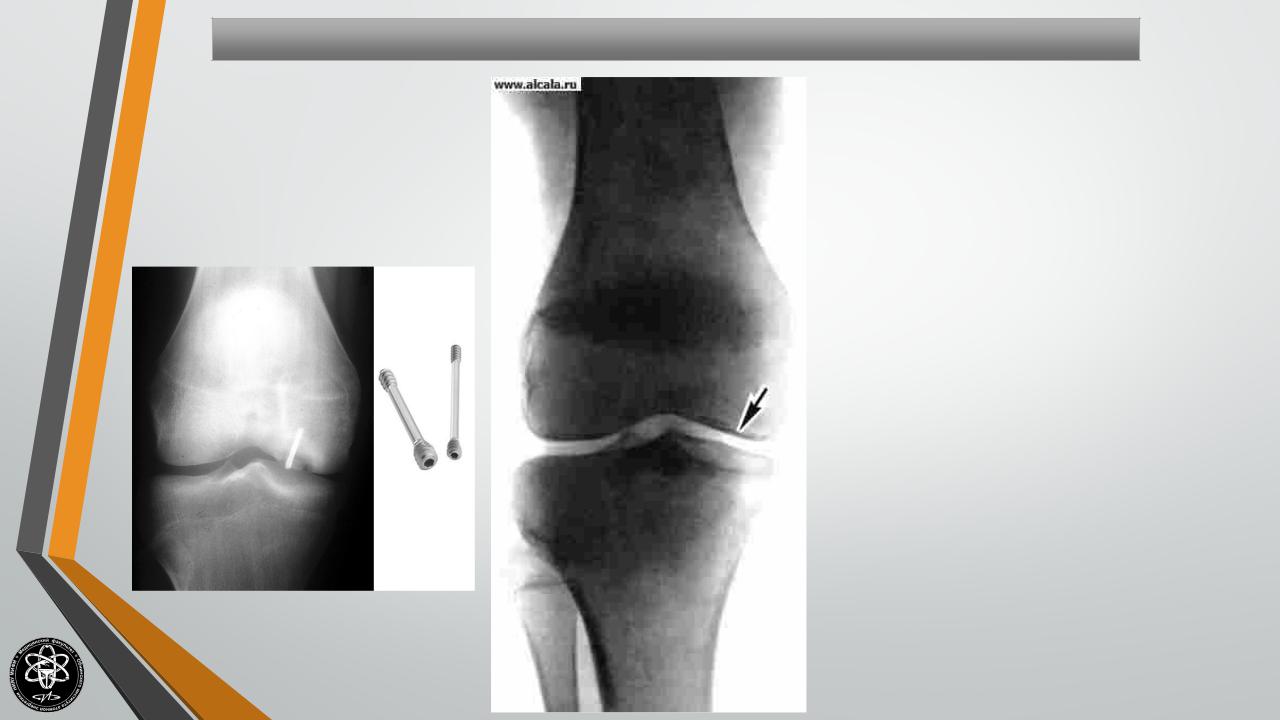

Частичные остеохондропатии суставных поверхностей (Болезнь Кенига)

Обычно развиваются в возрасте от 10 до 25 лет, чаще встречаются у мужчин. Около 85% частичных остеохондропатий развивается в области коленного сустава.

Как правило, участок некроза появляется на выпуклой суставной поверхности. В последующем поврежденная область может отделиться от суставной поверхности и превратиться в «суставную мышь» (свободно лежащее внутрисуставное тело). Диагностика проводится путем УЗИ или МРТ коленного сустава.

На первых стадиях развития остеохондропатии проводится консервативное лечение: покой, физиотерапия, иммобилизация и т.д. При образовании «суставной мыши» и частых блокадах сустава показано оперативное удаление свободного внутрисуставного тела.